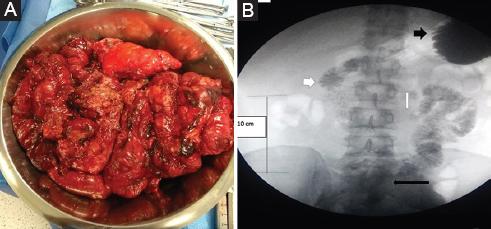

Inicia su padecimiento el 15 de febrero de 2018 con dolor abdominal, vómito, náusea e incapacidad para evacuar. Dos días después acude a un hospital de segundo nivel, se le diagnostica obstrucción intestinal y se le realiza laparotomía exploradora, con hallazgos de necrosis de 10 cm de yeyuno, por lo que se realizan resección y anastomosis término-terminal. Con mala evolución, se opera al sexto día por obstrucción, pero solo se realiza laparotomía con toma de biopsia y se le envía a un hospital de tercer nivel para protocolo diagnóstico, inicio de nutrición parenteral total y manejo de la obstrucción intestinal. Es sometido a una nueva intervención el día 7 de marzo por salida de material intestinal en el tercio inferior de la herida quirúrgica, y se evidencian múltiples laceraciones en cuerda de violín en la pared antimesentérica del intestino, secundarias a una lesión traumática por el material utilizado (polipropileno) para el cierre de la aponeurosis en la cirugía previa, además de adherencias Zulkhe II-III. Se decide la resección en bloque del intestino dañado (Fig. 1), dejando únicamente un remanente de yeyuno a 40 cm desde el ángulo de Treitz y la totalidad del colon. Se realizó una anastomosis yeyuno-colónica con engrapadora GIA 80 mmHg y se cerró la cavidad abdominal. El manejo de la sepsis fue acorde a las guías actuales.

Figura 1 A: intestino resecado. B: medición del remanente de intestino, estómago (flecha negra corta), duodeno (flecha blanca corta), ángulo de Treitz (flecha blanca larga) y fuga de medio de contraste en el yeyuno (flecha negra larga).

En el tercer día posquirúrgico el paciente presenta fuga de material intestinal y es necesario intervenir quirúrgicamente, con los siguientes hallazgos: enfermedad adherencial grave Zulkhe IV, imposibilidad de disecar el yeyuno por adherencias firmes al sigmoides, y necrosis de la cara anterior del ciego. Se disecan los bordes necróticos, se remodela la anastomosis y se colocan drenajes en las caras anterior y posterior de la anastomosis. En el posoperatorio mediato se evidencia fuga, y debido a la imposibilidad de tratamiento quirúrgico se decide tratarla como fístula de alto gasto. Se inicia terapia antisecretora con omeprazol 80 mg al día en infusión y loperamida 16 mg/día, además de continuar con nutrición parenteral 2400 kcal/día y suplementación multivitamínica. Se realiza tránsito intestinal con medio de contraste hidrosoluble para determinar la cantidad de intestino remanente, siendo aproximadamente de 40 cm desde el ángulo de Treitz (Fig. 1). Además, se realiza estudio en colon por enema con medio hidrosoluble, verificando la permeabilidad del tracto inferior.